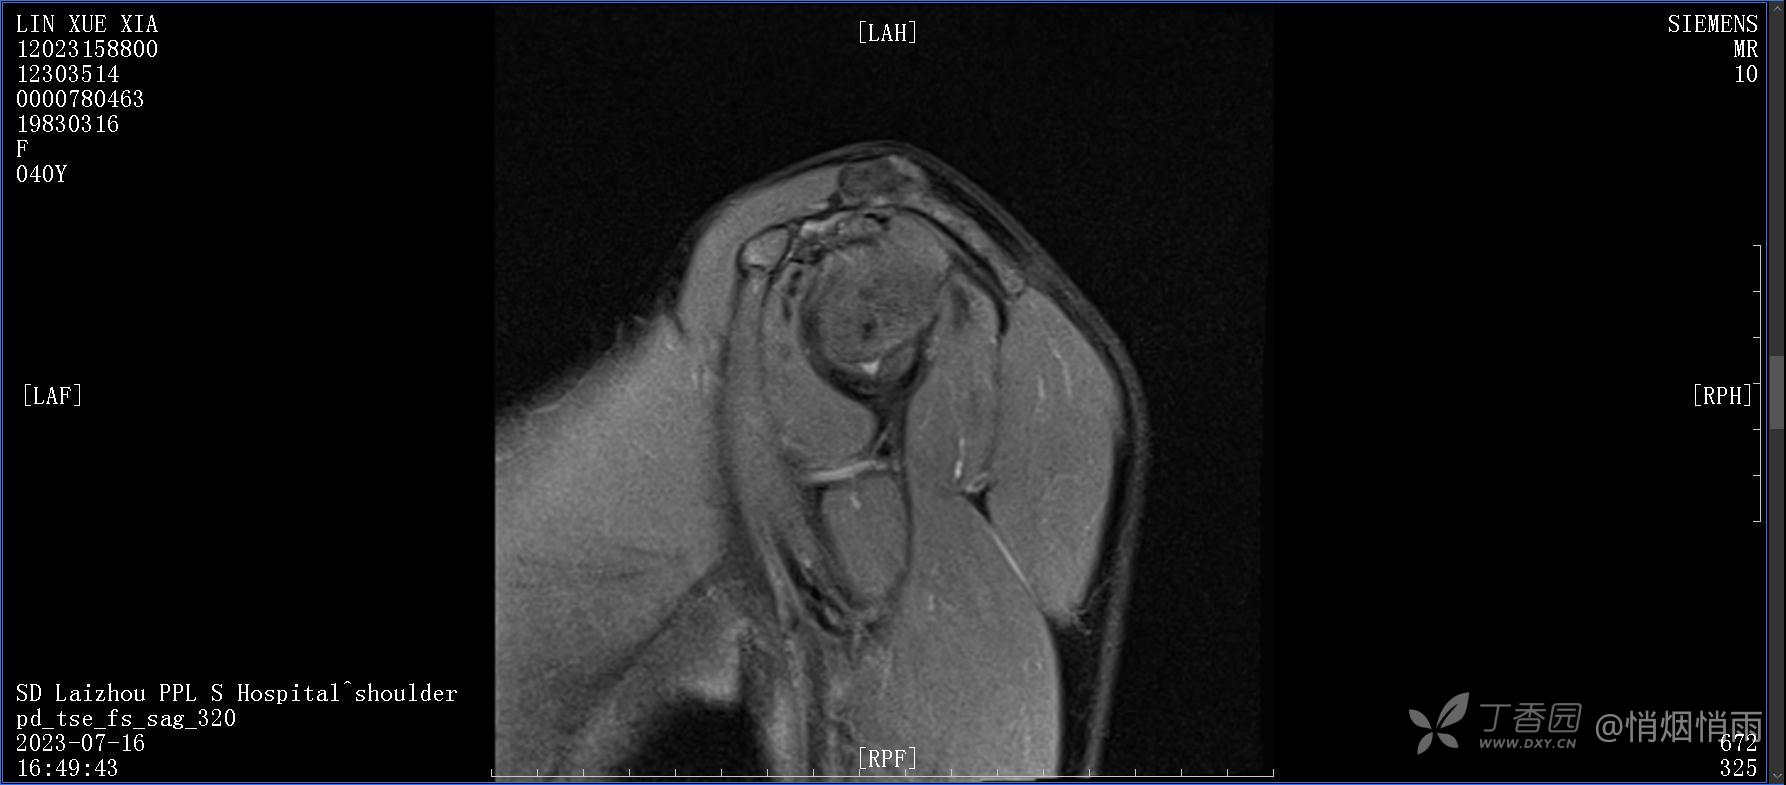

查体:右肩关节局部轻度肿胀,肩胛区压痛明显,痛处不固定,肩关节痛性活动受限,jobe test(+),lift -off test(+),中指、环指感觉较余指减退,余肢端感觉及血运情况可。

目前的诊断,暂时依据辅助检查诊为肩袖损伤,但是患者疼痛的性质和特点,却不是单纯的肩袖损伤所致。考虑过胸廓出口综合征,但是该疾病会出现肩胛区的疼痛吗?(由于考虑到费用的问题,没再进行下一步的检查)带状疱疹会有如此的症状吗?